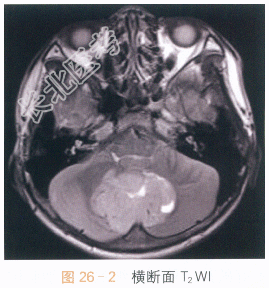

男,9岁,头痛4月余。

读片分析:头颅横断面T₁WI见小脑蚓部巨大软组织肿块影,呈不均质低信号,形态不规则,边界不清;横断面T₂WI可见病灶呈不均质高信号,周围可见瘤周水肿;增强扫描肿瘤部分可见不均质强化。